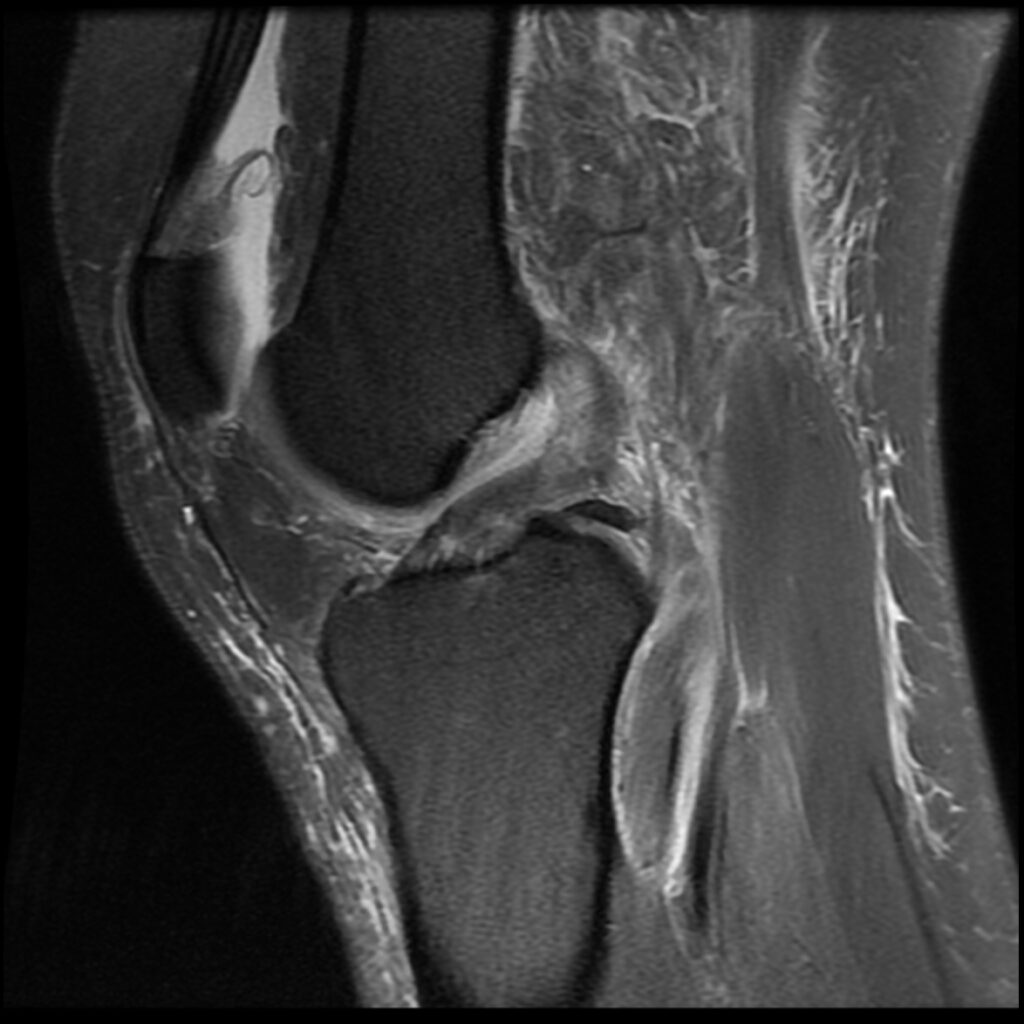

Patient C, age 44, was jumping on a trampoline when her foot got caught during rebound landing and forced the knee to extend and twist, tearing her ACL and medial meniscus and causing a Segond’s fracture, a posterolateral compression injury seen on the T2 sagittal MR images. Immediately upon becoming aware of her ACL injury, she asked my staff if she could put her “before & after” MR scans on my practice’s website after it healed. The initial treatment and aftercare were the same as patient D, aspirating any effusion and treating the posterolateral origin of the ACL. At 8-week follow-up, her knee was treated with hypertonic dextrose, with the collateral ligaments being treated with DGP. She was treated again at 16 weeks with another autologous PRP treatment of the knee joint, ligaments, and tendons. She was released to full sports and activities at 18 weeks post-injury. Subsequent MR scan revealed complete recovery of her ACL. Low grey signal replaced the original high signal intensity tear in the meniscus, appearing healed. Her knee was reported to be symptom-free at 5-year follow-up.

Patient C Before

Patient C After